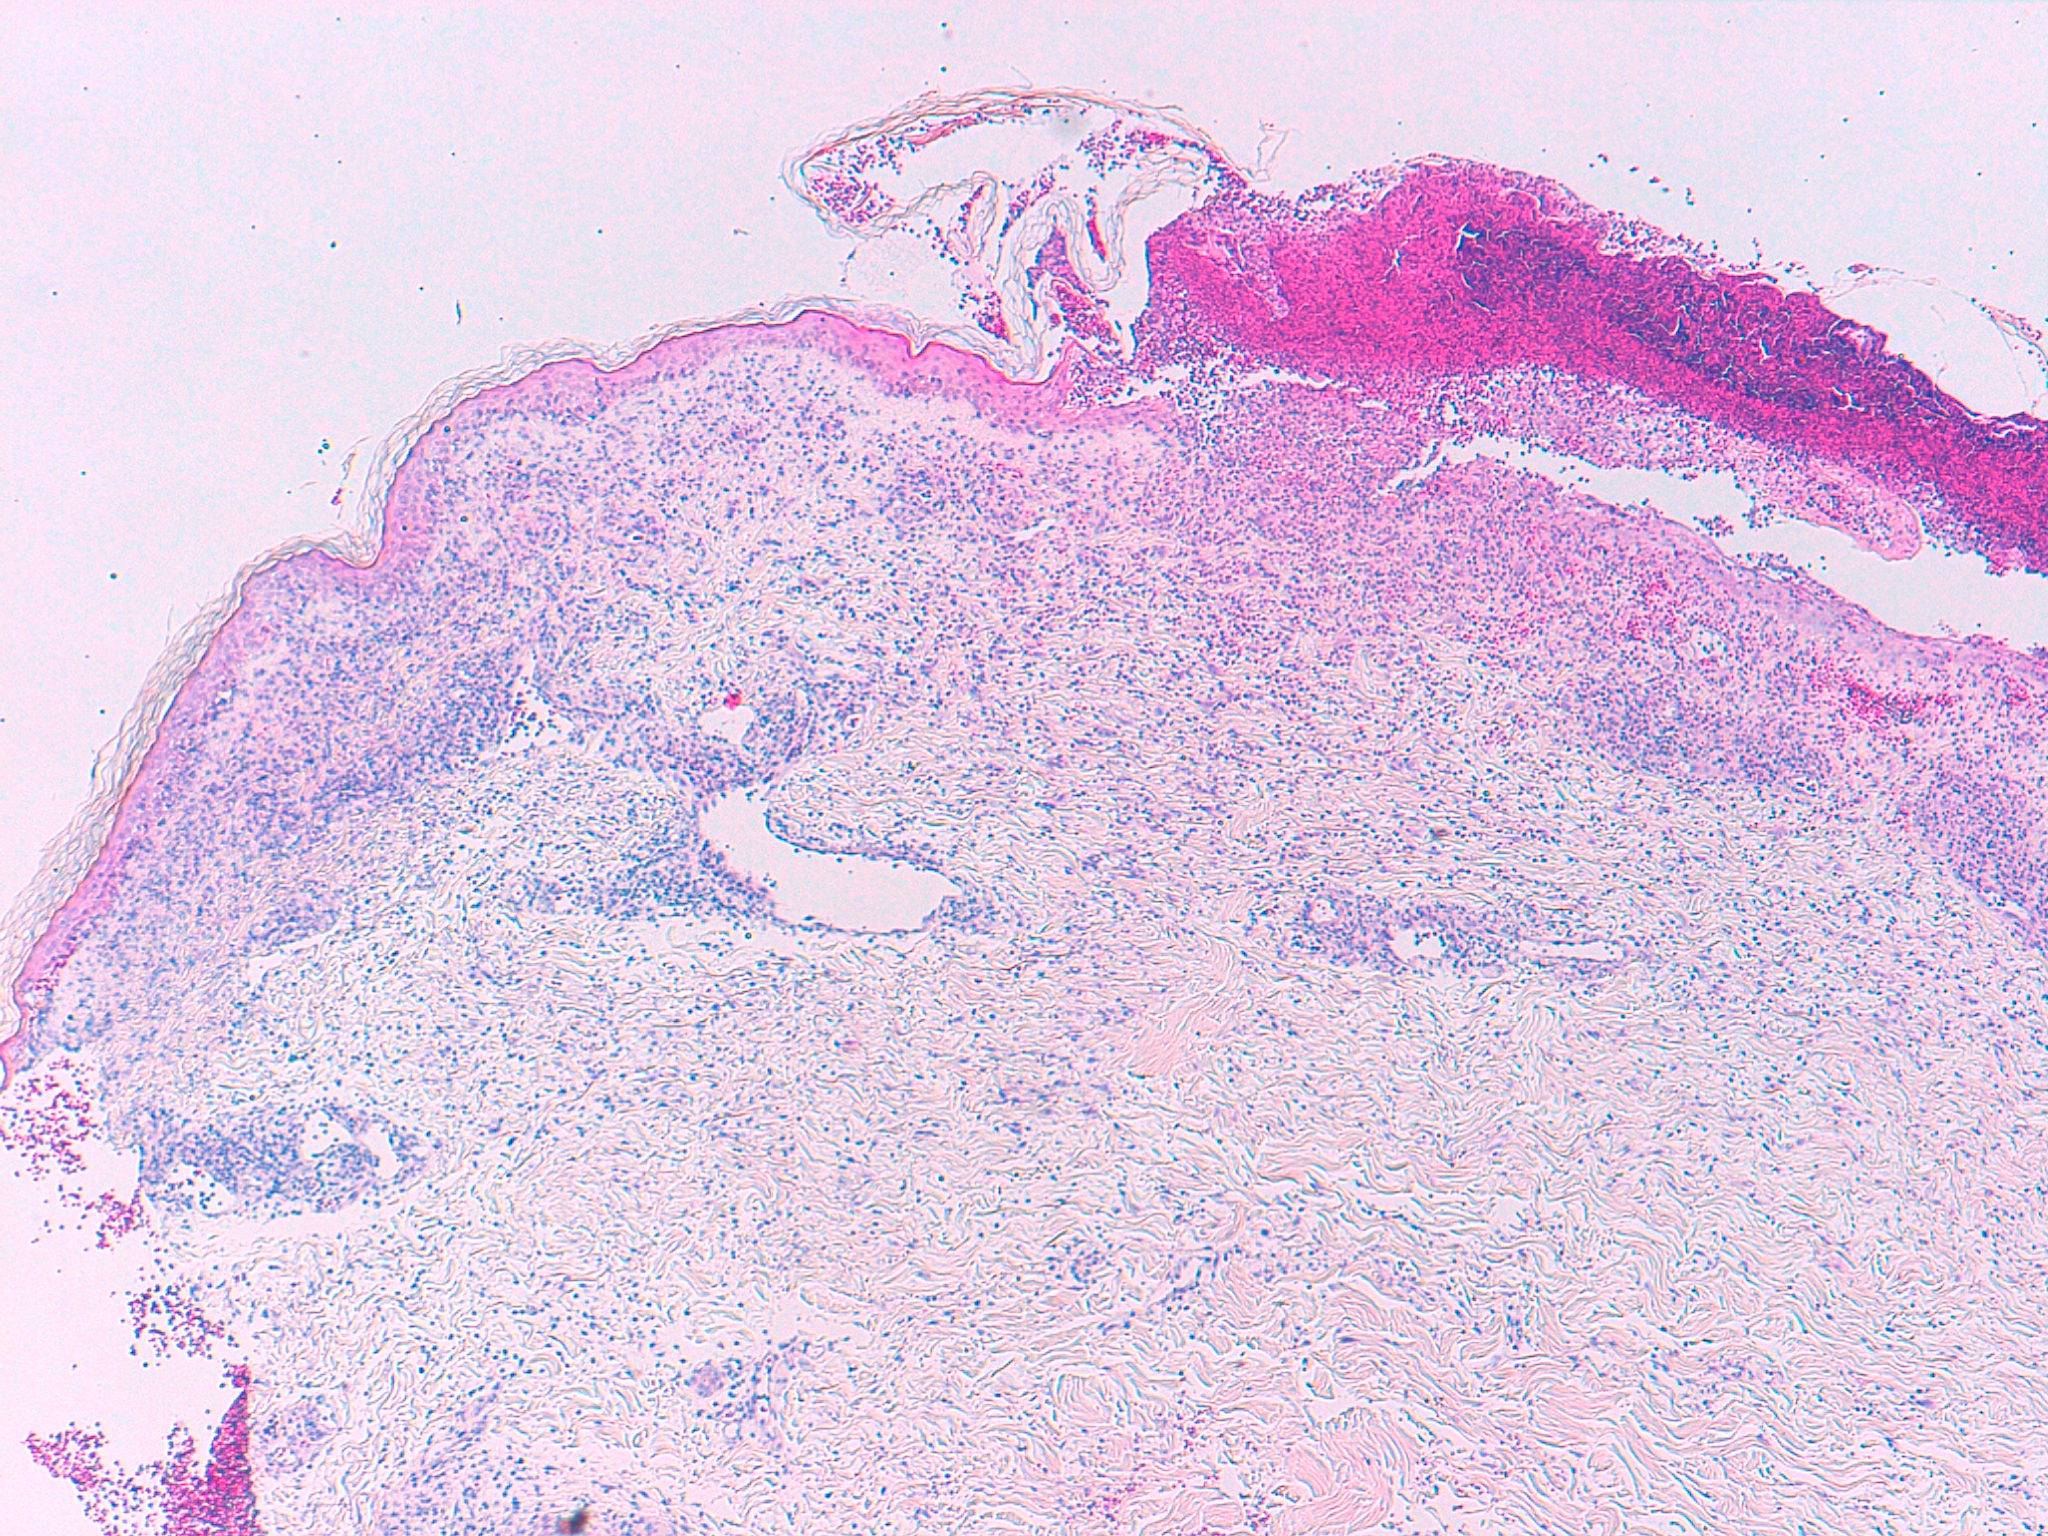

Pruebas complementarias:  Se practicaron 2 biopsias. Una de las lesiones ampollares y otra de piel perilesional.

Histología:  Tinción con hematoxilina-eosina (Figuras 3 y 4, HEx40 y HEx200 respectivamente) e Inmunofluorescencia directa (Figura 5, IFD para IgG x200).